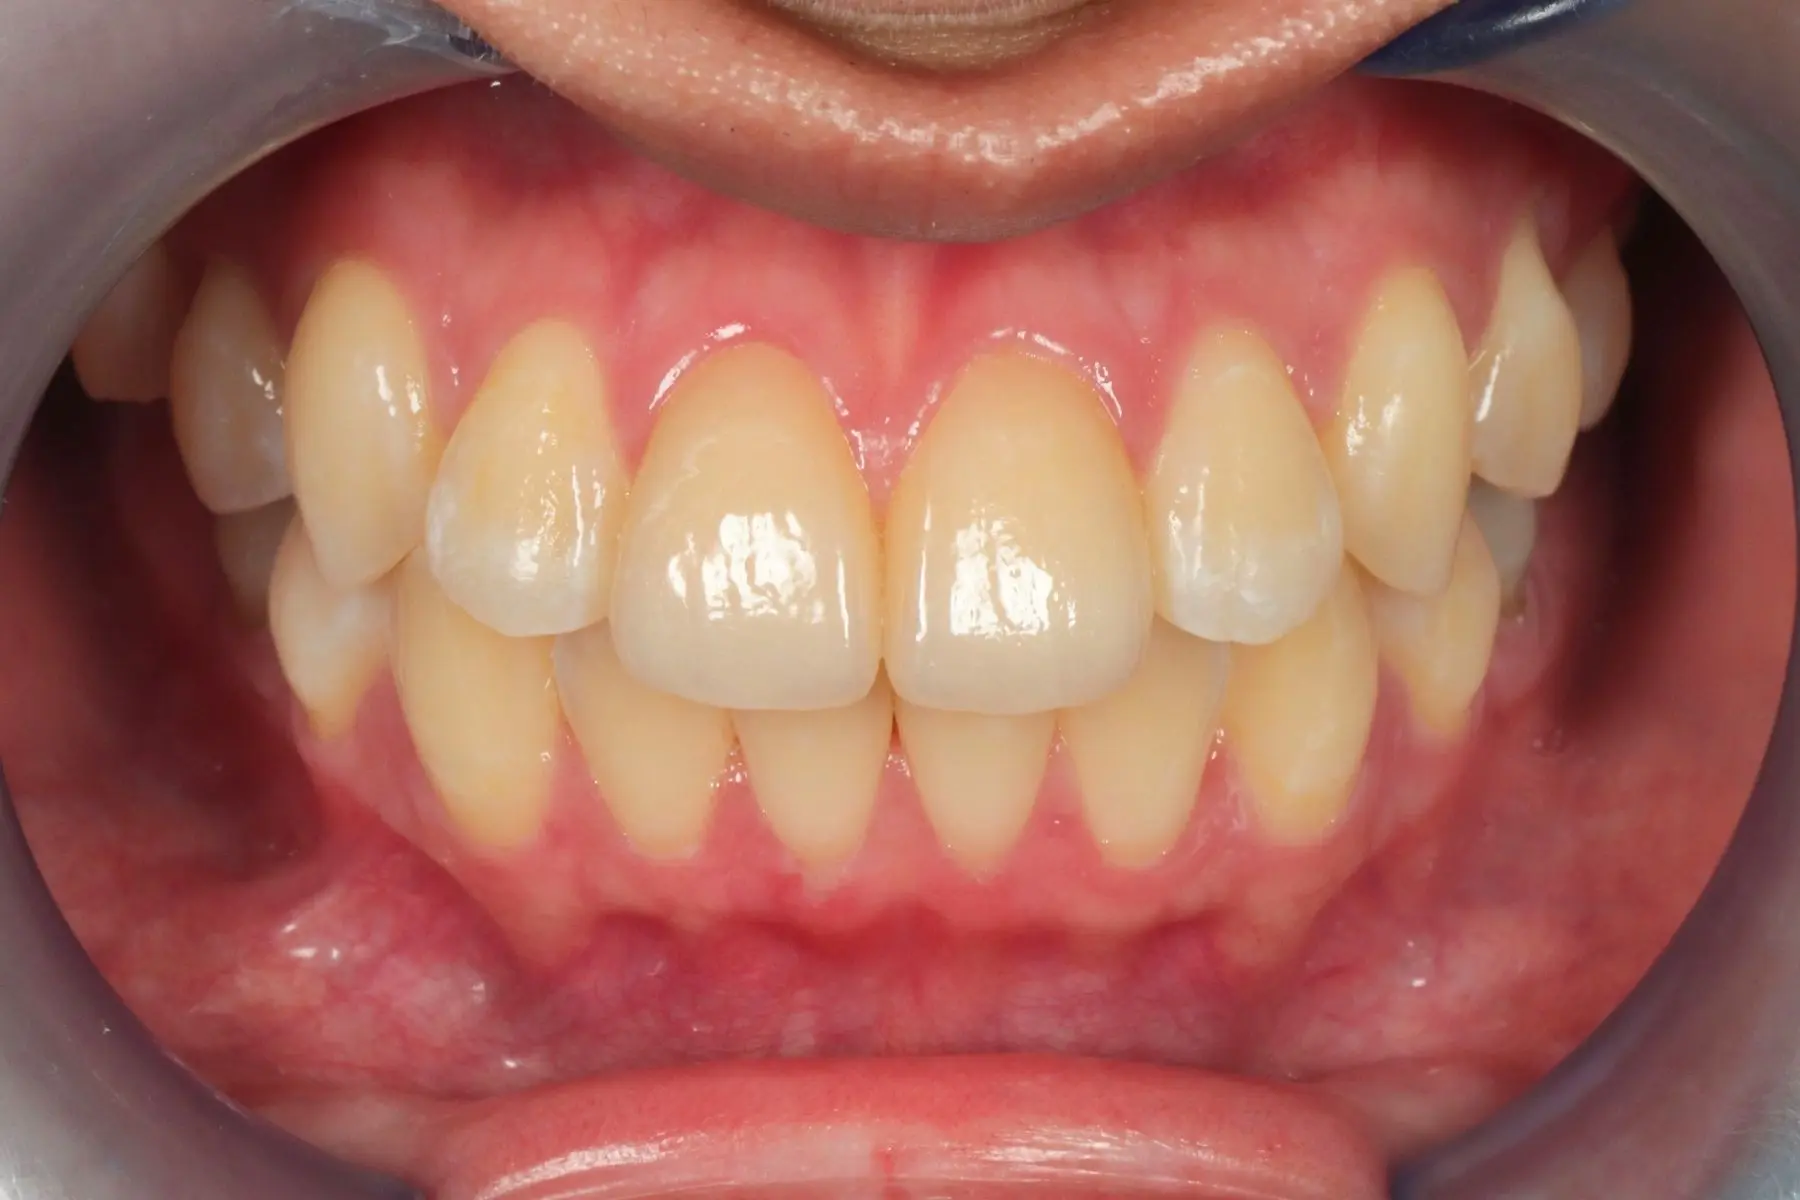

• 術前 43

術後 41

仿生美學樹脂

主治醫師

• 陳暐文

治療時間

單次療程

主訴

矯正完成下排前牙出現黑三角